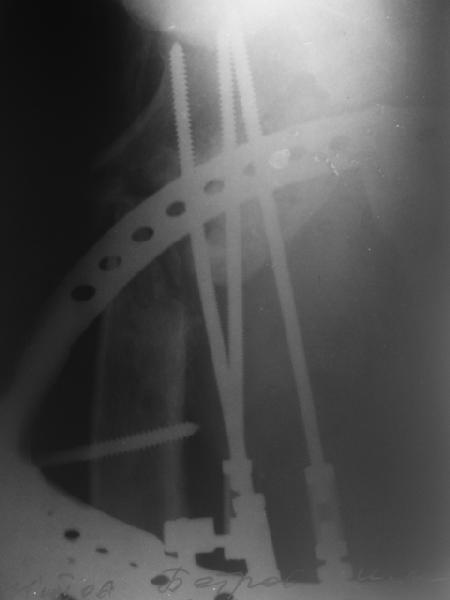

Возможно, пример (в приложении) поможет Вам определиться с выбором тактики лечения (у нашего пациента, кроме тугого ложного сустава вертельной области, сложная деформация н/3 бедренной кости; т.к. это не имеет значения к обсуждаемой теме - оставил "за кадром"). Как Вы видите, мы в данном случае не вводили чрескостные элементы в зону установки имплантата. При отказе от наложения опоры на таз (кстати, она не обязательно может быть громоздкая спицевая; арки со стержнями-шурупами, введенными в крыло подвздошной вполне достаточно) "не удивляйтесь", если опора со стержнями-шурупами, введенными в вертельной области в скором времени дестабилизируется, возникнет воспаление мягких тканей у чрескостных элементов. Такая опора "имеет на это право": нагрузка конечности от вершины дистального фрагмента до кончиков пальцев ляжет на нее. А двух-трех введенных рядом стержней-шурупов, как их не разноси от фронтальной плоскости, в данном

случае явно недостаточно для адекватной фиксации. + для того, чтобы выбрать оптимальные чрескостные элементы для промежуточной и дистальной опор, можете воспользоваться атласом

В приложении пример пациента, близкого по картине к тому, что представил Виктор (варус и смещение периферического отломка на поперечник кзади). Сделали как раз то, что Виктор исходно намеревался - аппаратная коррекция и затем гамма.